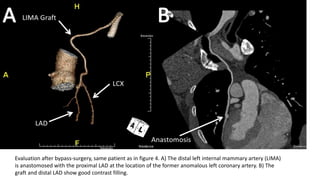

Evaluation after bypass-surgery, same patient as in figure 4. A) The distal left internal mammary artery (LIMA)

is anastomosed with the proximal LAD at the location of the former anomalous left coronary artery. B) The

graft and distal LAD show good contrast filling.

Evaluation after bypass-surgery,same patient as in figure 4. A) The distal left internal mammary artery (LIMA) is anastomosed with the proximal LAD at the location of the former anomalous left coronary artery. B) The graft and distal LAD show good contrast filling.